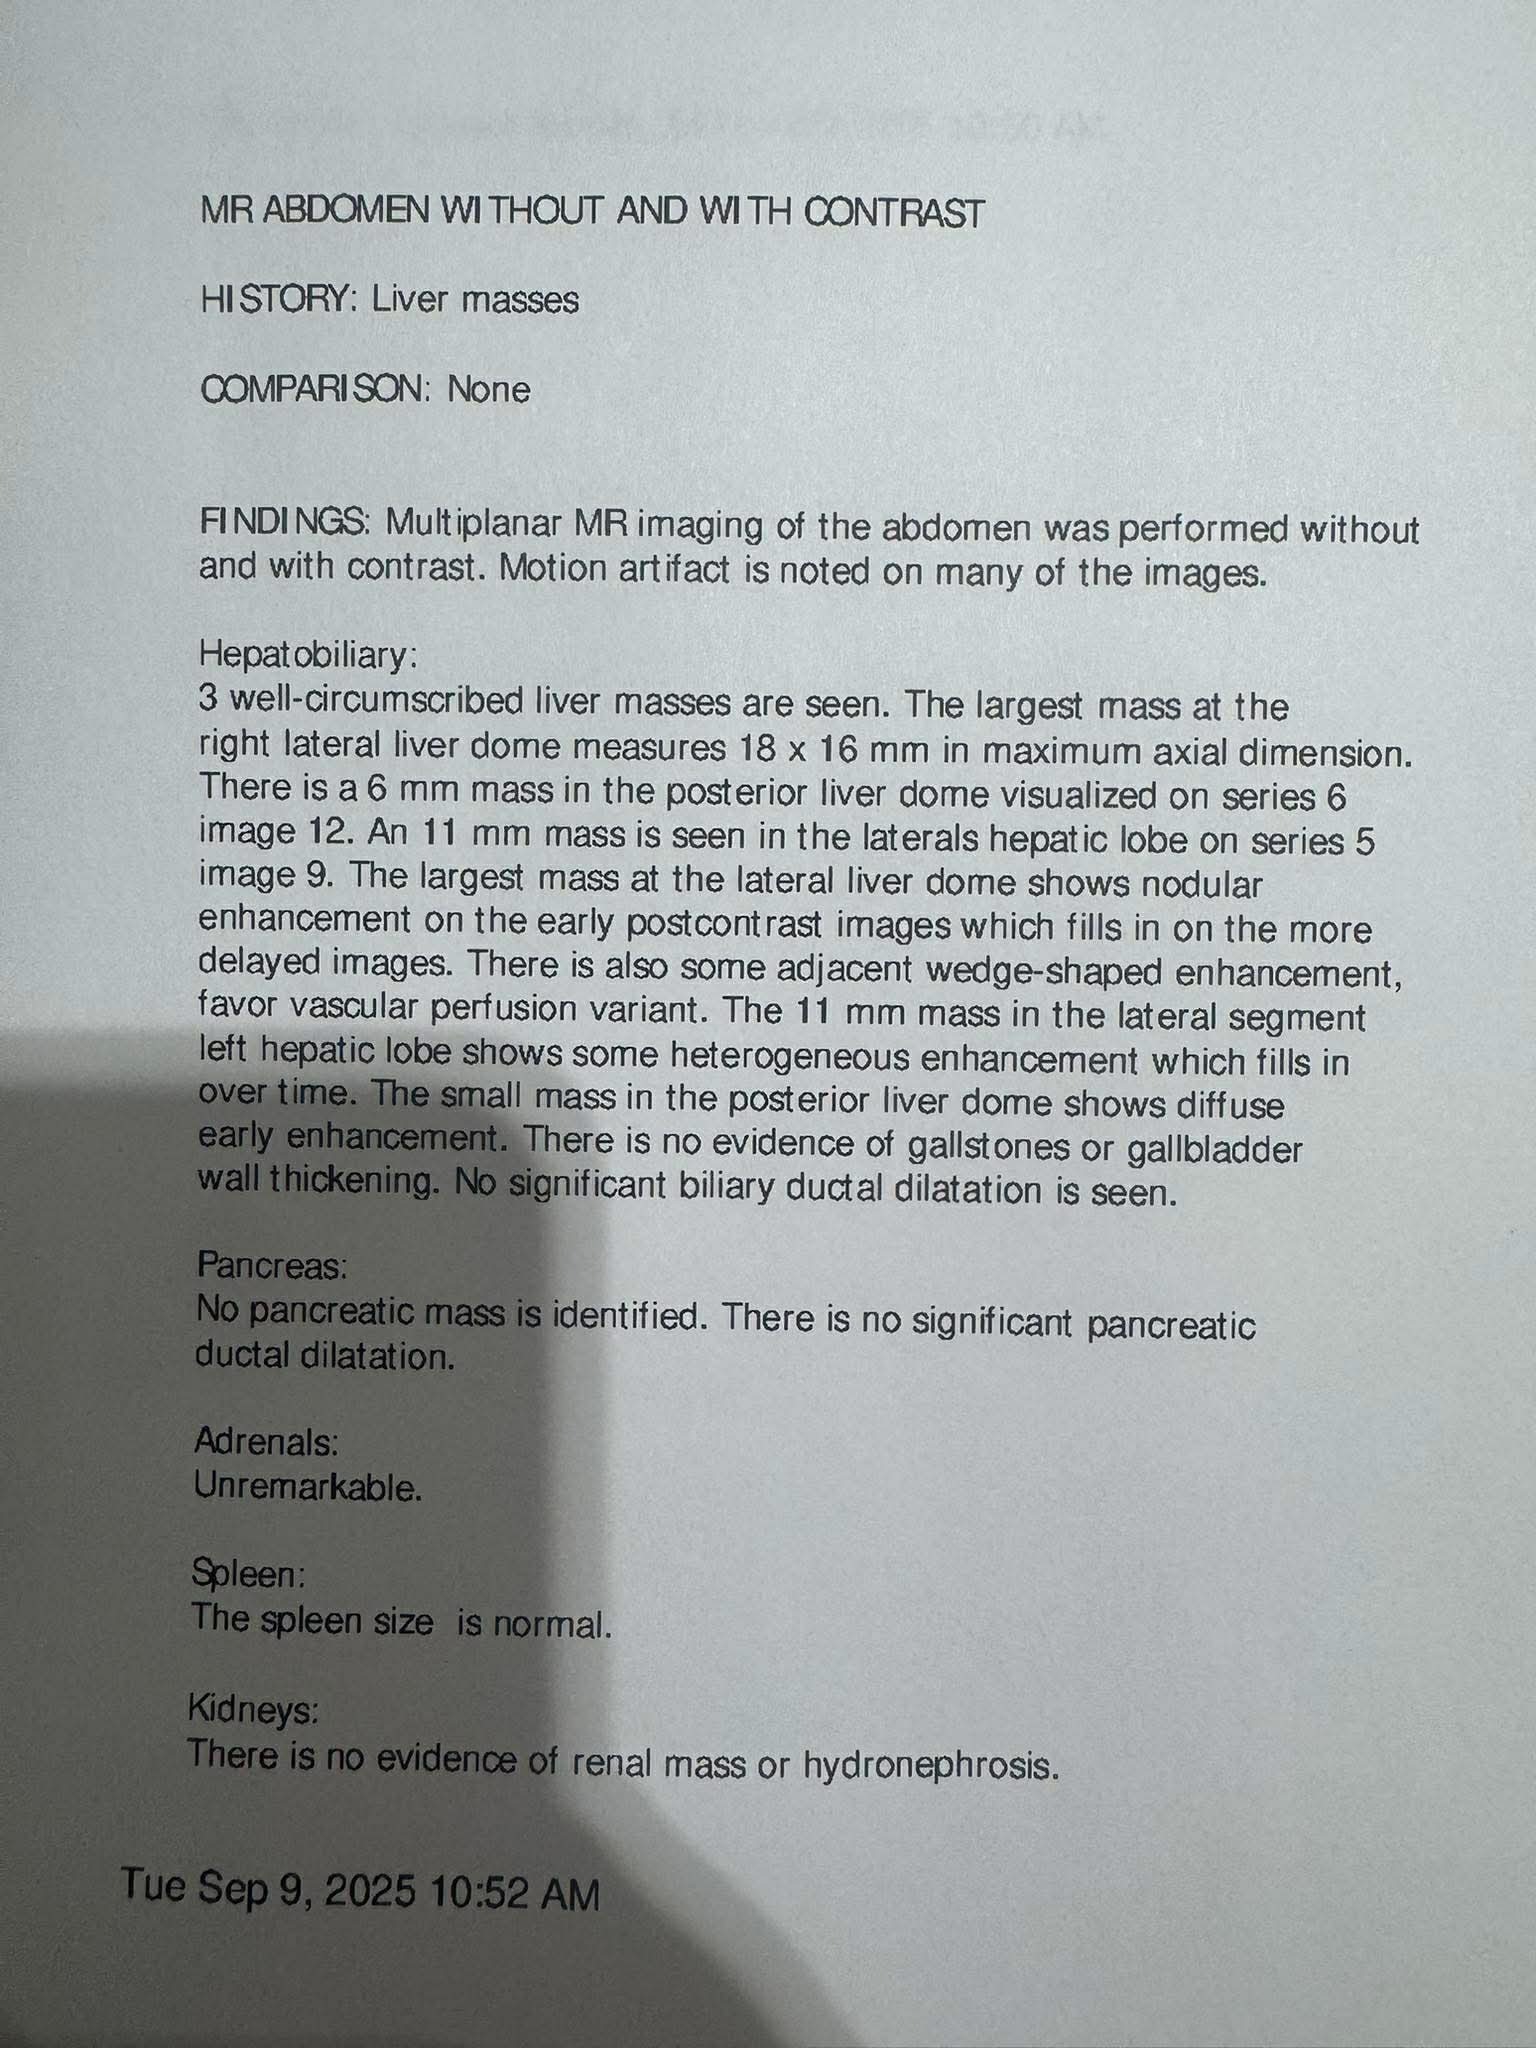

-Derek currently has two potentially deadly infections in his spinal cord, along with IDH Mutant or Astrocytoma, which is a brain cancer that there is currently no cure for. On top of all of this, he has developed 3 masses on and in his liver. With his current regimen of over 20 pills a day, driving to Lexington for appointments 6-8x a week and to Vanderbilt often, as well being a Dad and continuing his duties there, the financial burden has been significant. He has been fighting disability which feels like a losing battle for 2 years. -

Derek has been facing an ongoing battle with brain cancer and other medical issues. Most recently, he learned that he has a severe infection on his spinal cord, a cancerous tumor in his brain, as well as his liver. He has had to have a PICC line put in, and will be down for at least 8-10 weeks, if not longer. Insurance is being a pain and not wanting to cover many parts of his treatment, including home health, which is causing him to have to stay in the hospital, and miss valuable time with his son and best friend, Jayden.